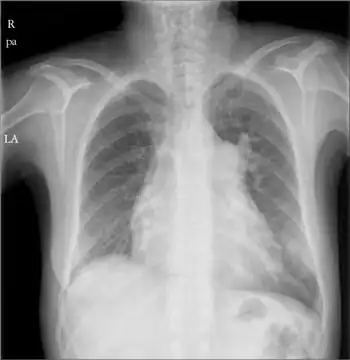

Right atrial enlargement

| Right atrial enlargement (P pulmonale) | |

Right atrial enlargement (RAE) is a form of cardiomegaly, or heart enlargement. It can broadly be classified as either right atrial hypertrophy (RAH), overgrowth, or dilation, like an expanding balloon. Common causes include pulmonary hypertension, which can be the primary defect leading to RAE, or pulmonary hypertension secondary to tricuspid stenosis; pulmonary stenosis or Tetralogy of Fallot i.e. congenital diseases; chronic lung disease, such as cor pulmonale. Other recognised causes are: right ventricular failure, tricuspid regurgitation, and atrial septal defect.[1]

It is characterized by a high P wave amplitude (P pulmonale), i.e. a height greater than 2.5 mm in inferior ECG leads (II, III, aVF); and greater than 1.5 mm in right sided precordial leads (V1, V2). [2]

Large "a" waves on the JVP waveform can also aid in diagnosis.